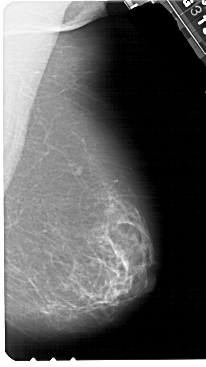

A_1552_1.RIGHT_MLO

A_1552_1.RIGHT_CC

RIGHT_CC LINES 5491 PIXELS_PER_LINE 2866 BITS_PER_PIXEL 12 RESOLUTION 43.5 NON_OVERLAY

RIGHT_MLO LINES 5491 PIXELS_PER_LINE 3076 BITS_PER_PIXEL 12 RESOLUTION 43.5 NON_OVERLAY